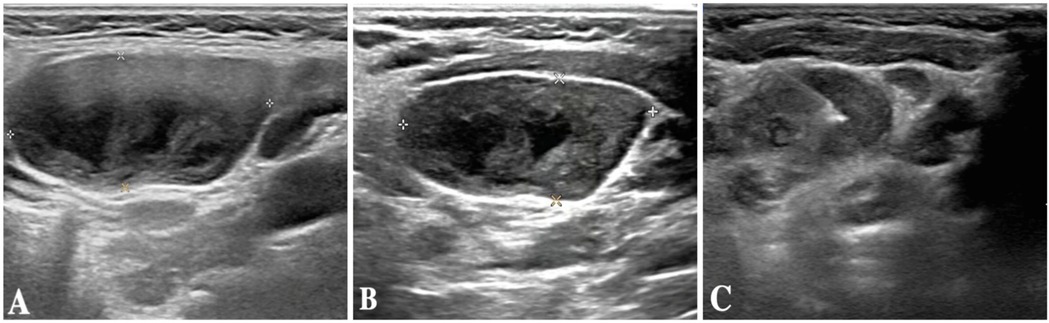

The child was evaluated in our infectious disease clinic on August 7, 2024, where a neck ultrasound revealed bilateral suppurative lymphadenitis (Figure 1A), leading to hospitalization on August 8, 2024. Laboratory workup during admission showed: erythrocyte sedimentation rate (ESR) 39 mm/h and positive nucleic acid detection for Streptococcus pneumoniae and Haemophilus influenzae in respiratory pathogen testing. Procalcitonin, immunoglobulin levels, PPD testing, and blood cultures were unremarkable or negative. A provisional diagnosis of acute suppurative lymphadenitis was established, and empirical antibiotic therapy with cefoperazone-sulbactam was initiated. Follow-up ultrasound on August 12, 2024, showed no significant improvement in lymphadenopathy (Figure 1B). Repeat laboratory testing on August 15, 2024, demonstrated persistent inflammation (CRP: 26.27 mg/L, ESR: 43 mm/h) with markedly elevated interleukin-6 (44.47 pg/ml) and interleukin-10 (22.15 pg/ml). Due to inadequate clinical response, ultrasound-guided aspiration of the right cervical abscess was performed on August 15, 2024 (Figure 1C). While Gram staining and cultures of the aspirate were negative, mNGS identified 23,255 sequence reads of L. pneumophila with 21.07% genome coverage (Table 1 and Figure 2). Antimicrobial therapy was adjusted to intravenous azithromycin and trimethoprim-sulfamethoxazole. Although the neck mass softened and reduced in size, ultrasound-guided re-aspiration was required on August 23, 2024, due to persistent liquefaction. After 18 days of hospitalization, the child was discharged on August 26, 2024, with continued oral azithromycin and trimethoprim-sulfamethoxazole. However, trimethoprim-sulfamethoxazole was discontinued after 8 days due to allergic reaction, and therapy was successfully completed with oral rifampin. The child patient was treated with azithromycin for a total of 14 days, starting from intravenous injection for 7 days and oral administration for 7 days on August 17, 2024. Rifampicin was taken orally for a week, starting from August 30, 2024. During hospitalization, the patient demonstrated progressive improvement in laboratory and clinical parameters, including normalization of white blood cell count, reduction in CRP levels, resolution of fever, and stabilization of other inflammatory markers (Figure 3).

Three-panel ultrasound image sequence labeled A, B, and C. Panel A shows a cross-sectional view with a distinct oval-shaped dark area. Panel B presents a more rounded dark area with a defined edge. Panel C displays an irregular shape with varied shading, less defined than A and B.

Figure 1. (A) Neck ultrasound results of the patient on August 7, 2024. (B) Neck ultrasound results of the patient on August 12, 2024. (C) Neck ultrasound results of the patient on August 15, 20.